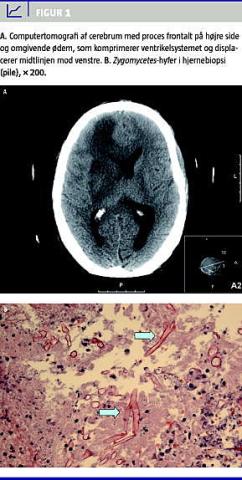

Der kom tiltagende sinuitissymptomer med blodigt nasalsekret og periorbital hævelse. CT af ansigtsskelettet viste sløring af sinus maxillaris og ethmoidalis. PÂ dag 78 blev patienten ukontaktbar, og CT af cerebrum viste nytilkommen proces i højre frontallap (Figur 1 A). I biopsi herfra fandt man zygomycosis (Figur 1B). Til trods for et normaliseret neutrofiltal og behandling med amphotericin B (AmB) og posaconazol endte forløbet fatalt på dag 105.

Postmortem viste immunhistokemisk undersøgelse af biopsi, at arten var Rhizopus oryzae.